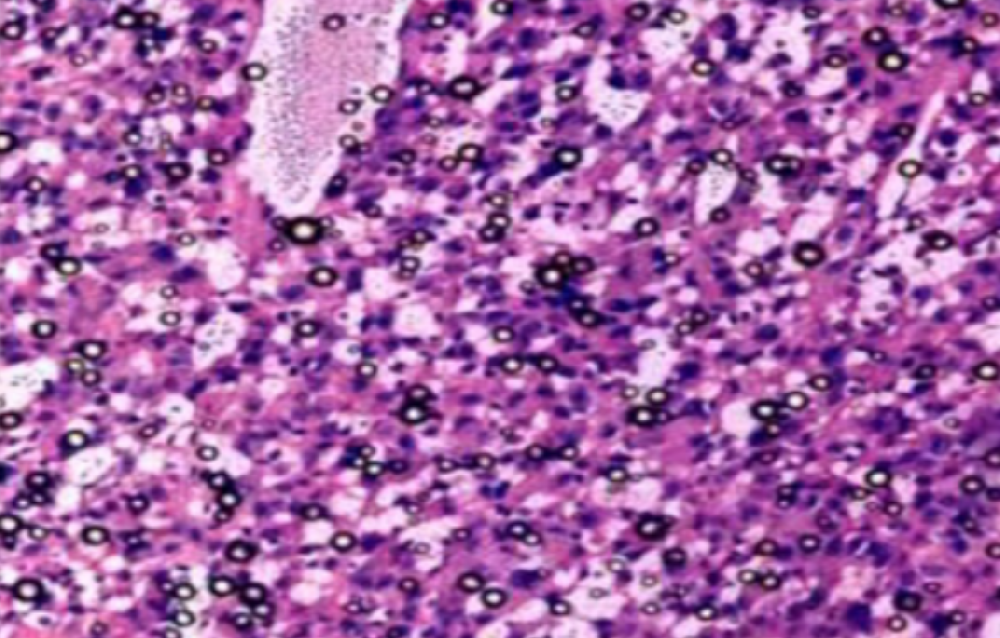

鹰潭组织病理学实验